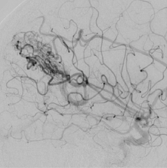

いわゆるカテーテル治療のことを言います。細いカテーテルを、AVMを栄養している動脈へ誘導して、「塞栓物質」と呼ばれるものを使用して、AVMへの血流を遮断する方法です。「塞栓物質」は、nBCAと呼ばれる医療用の接着剤や、Onyxと呼ばれるポリマーが多く使用されます。 脳を直接触る手術ではないため、患者さんへの負担は少ない治療ですが、この治療のみでAVMを完治させることは困難です。このため、外科的摘出術や放射線外科治療の前段階の治療として、サイズを縮小させたり、血流を減少させることを目的に行われることが多い方法です。

CTやMRIに加えて、脳血管撮影を施行した上で、治療方針を決定しています。出血を起こしていないものに関しては、敢えて治療をせずに、経過観察を行う場合もあります。安全に摘出可能と判断できる病変に関しては、血管内治療による塞栓術を併用して、外科的摘出術を行います。摘出術が困難ですが、治療が必要と判断される病変に関しては、塞栓術を行った後に、放射線治療を行うことをお勧めしています。 当施設には、ガンマナイフやサイバーナイフが設置されておりませんが、関連施設にご依頼させて頂き、治療前後のフォローを綿密に行っております。